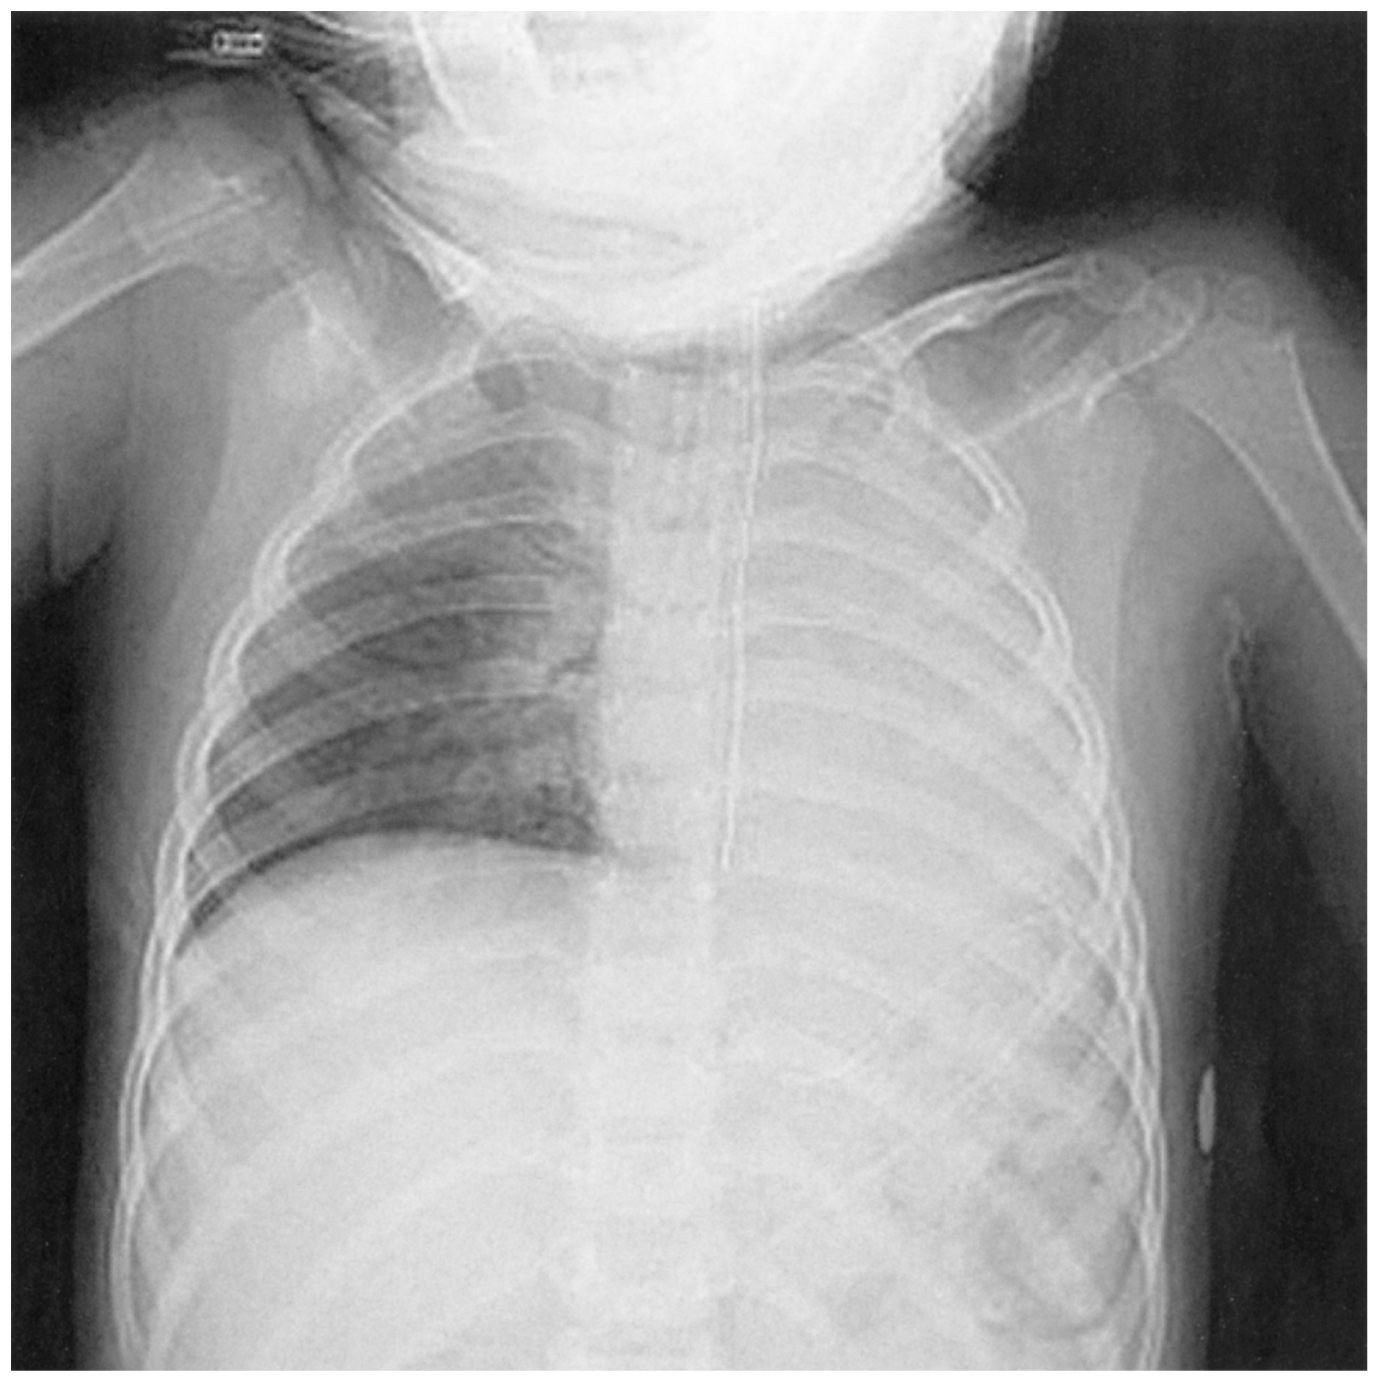

4歳の女児。急性脳症による意識障害のため小児集中治療室〈PICU〉で人工呼吸管理中である。今朝,SpO2が突然低下したため,研修医に報告があった。体温37.0℃。心拍数130/分,整。血圧92/50mmHg。呼吸数30/分(呼吸器設定:換気回数30/分,FIO2 0.4)。SpO2 81%。胸郭の動きは左右差がある。心音に異常を認めない。呼吸音は左側で著明に減弱している。腹部は平坦,軟で,腸雑音を聴取する。経鼻胃管は昨日と同じ固定位置で,胃液が吸引できる。気管チューブの固定テープにゆるみがあり,固定位置が2cm深くなっている。気管チューブから喀痰吸引を行い,チューブの閉塞はみられなかった。胸部エックス線写真を下に示す。

無料会員登録していただくと、実際の解説をすべて見ることができます。急性の呼吸困難を主訴とする疾患としては,喉頭浮腫,気道異物,自然気胸,気管支喘息,慢性閉塞性肺疾患の急性増悪などの呼吸器疾患,心不全(急性,慢性の急性増悪),肺血栓塞栓症などの循環器疾患が代表的である。この症例では呼吸器感染症と心不全が疑われるが,胸部エックス線写真は肺炎像というよりも両心不全を示唆する所見を示している。診断:心不全(両心不全)(Nohria分類wet and warm) 選択肢考察 ×a 強い呼吸困難,胸痛などにより安静が保てない場合には,血管拡張による前負荷軽減と,交感神経抑制による心筋酸素消費量の減少を目的としてモルヒネを使用する。この症例ではモルヒネが必要となるほどの興奮状態ではない。